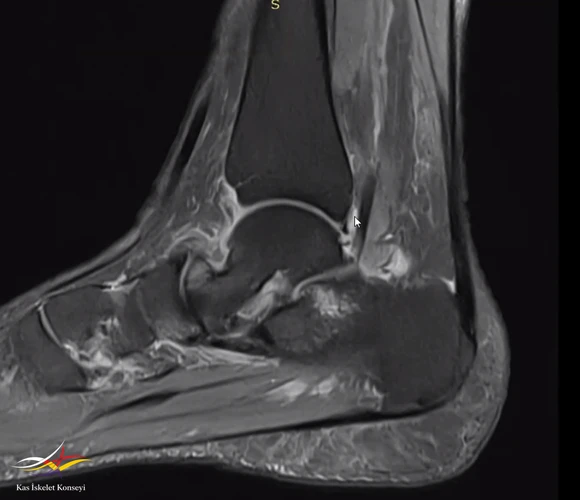

Resim 1. Ayak bileği MRG.